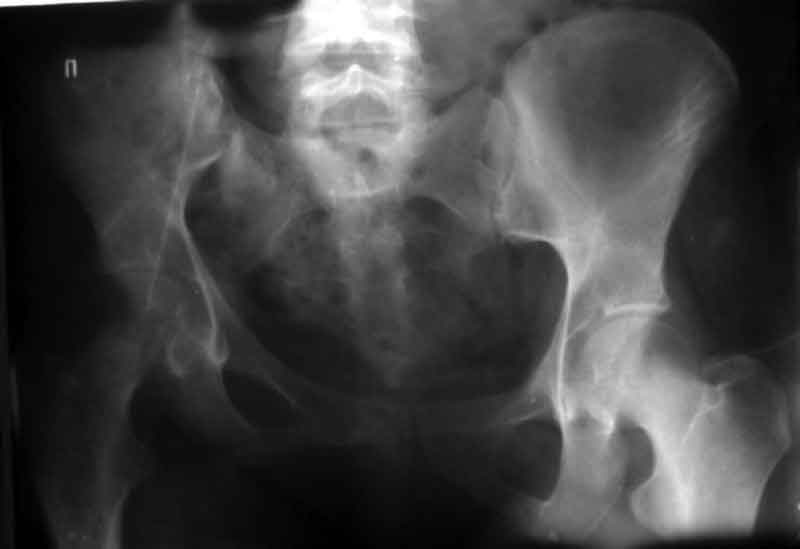

[Ortho] Застарелое повреждение таза

> прилагаю пример с такой же давностью травмы, репонировали аппаратом